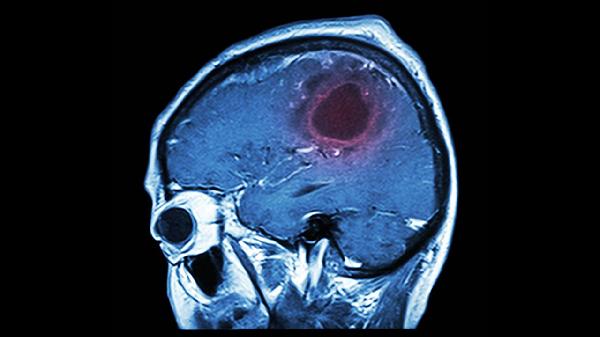

日常可进行游泳、羽毛球等仰头运动,每周3次以上能增强颈后肌群力量。饮食多摄入富含镁元素的食物如南瓜子、黑巧克力,避免高盐饮食诱发血管痉挛。保持规律作息,睡前1小时避免使用电子设备。若症状持续加重或伴随呕吐、视物模糊,需立即排查颅内病变。